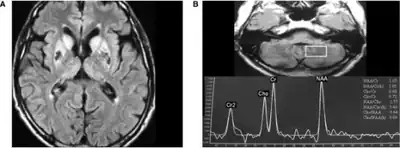

Neuroferritinopathy is most commonly diagnosed using MRI and other neuroimaging techniques.[1] MRIs help identify the iron deposits in the cerebellum, basal ganglia, and motor cortex common to neuroferritinopathy.[8] MRIs of affected individuals also show mild cerebellar and cerebral atrophy, or tissue breakdown, and gas cavity formation in the putamen.[8] Most importantly, the MRIs show misfolded ferritin proteins and iron deposits in the glial cells of the caudate, putamen, globus pallidus, cerebral cortex, thalamus, and purkinje cells, causing neuronal death in these areas.[8]

a)High signal caudate and lenticular nuclei b) long echo time in deep left cerebellum

MRI